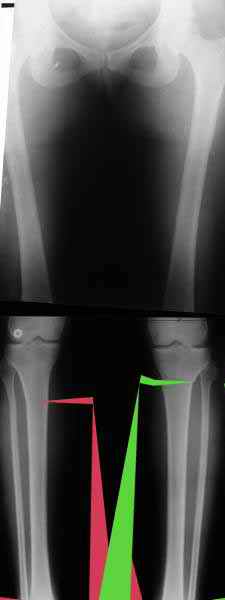

Из приведнной схемы не совсеим понял что означают разноцветные линии.

И зачем латерализация периферического фрагмента. Я всегда делаю медиализацию. См схему. И для данного случая медиализация подходит как нельзя лучше.

a> Из приведнной схемы не совсеим понял что означают разноцветные линии.

Черные - это нынешняя механическая ось. Красные - это планируемая правильная ось.

a> И зачем латерализация периферического фрагмента.

;-) Читайте Палея. Стр. 114-115.

a> Я всегда делаю медиализацию. См схему. И для данного случая

Медиализация - это чисто эстетический прием, как я понимаю. Поскольку если делать остеотомию ниже вершины деформации, для восстановления оси надо делать смещение по ширине, в данном случае как раз латерализацию.

А вот на схемке без осей - там на разных уровнях (который правильнее?) устранение варуса чисто открытым клином без медиализации-латерализации. Если как-то так сделать - этого недостаточно будет?